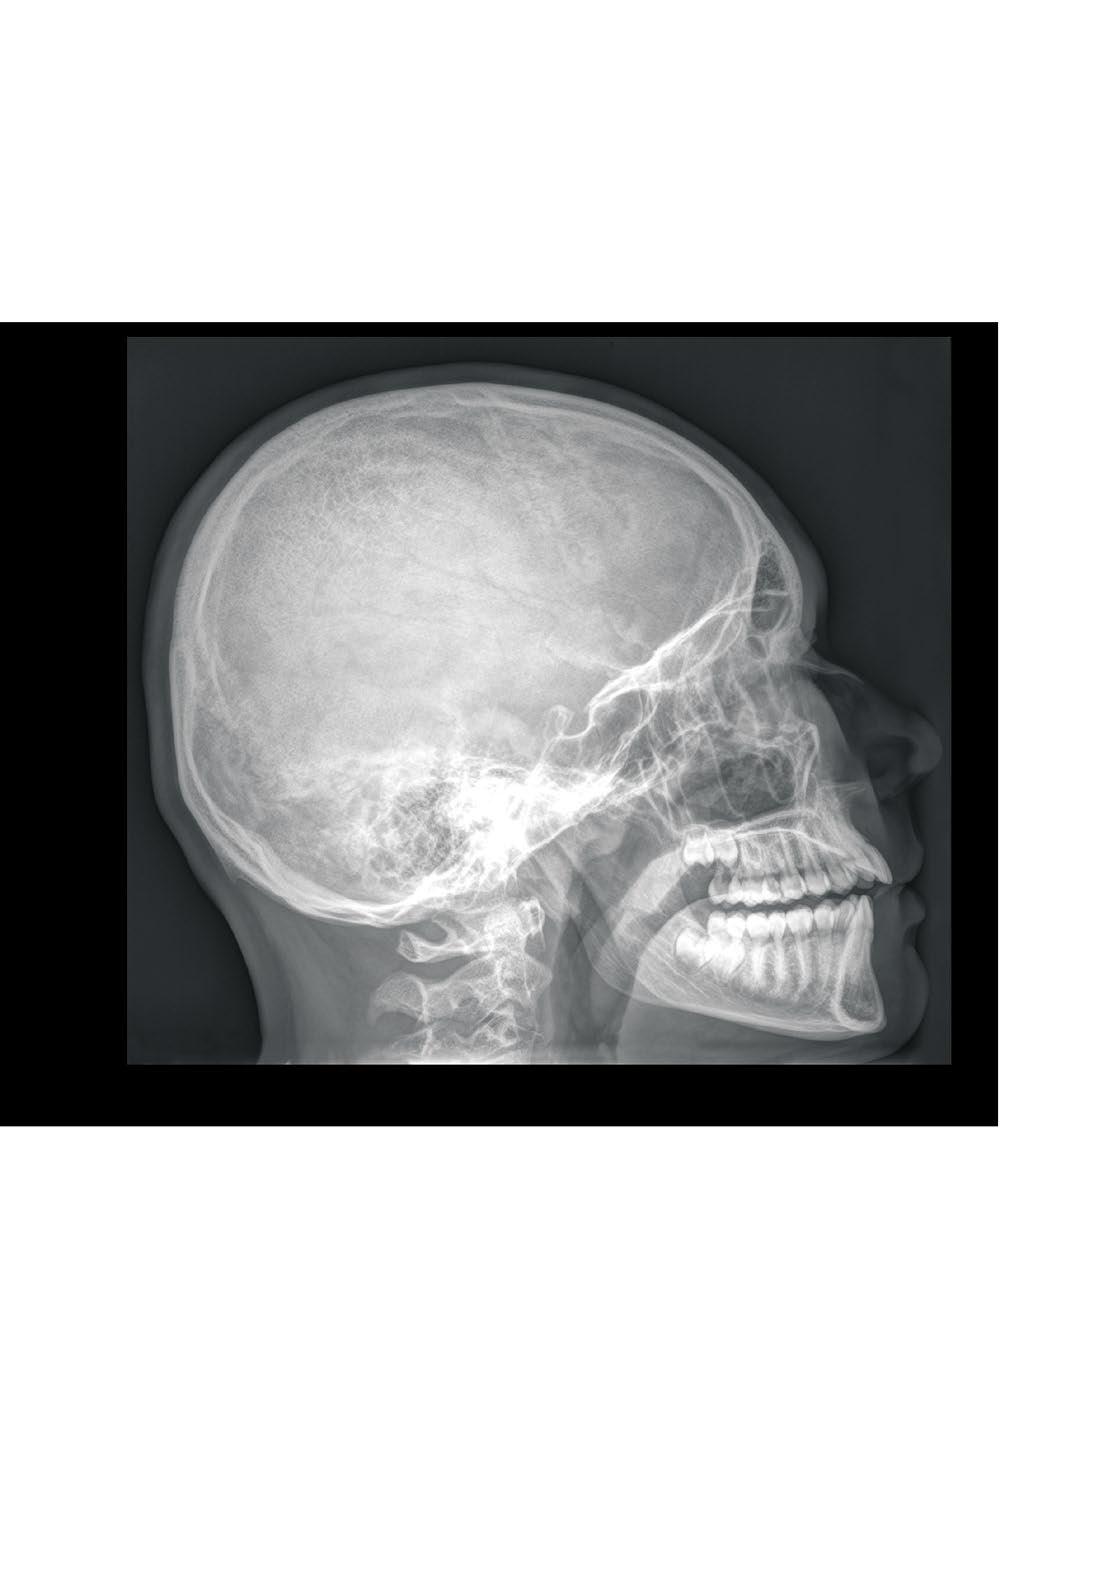

Skull, X-ray, lateral view, boy, 15 years Hlava

sutura coronalis sinus sphenoidalis

Cranium, RTG lebky, boční projekce, chlapec, 15 let

processus condylaris arcus atlantis anterior

dens axis canalis mandibulae processus mastoideus

cellulae mastoideae fossa hypophysialis

processus palatinus maxillae

lamina horizontalis ossis palatini

sutura lambdoidea

sutura squamosa

linea temporalis superior os parietale

os occipitale

foramen mastoideum

squama ossis temporalis

meatus acusticus externus processus mastoideus processus styloideus

os zygomaticum

sutura coronalis

sutura sphenoparietalis

sutura sphenofrontalis

ala major ossis sphenoidalis

glabella os lacrimale os nasale sulcus nasolacrimalis

maxilla spina nasalis anterior

foramen mentale

sulcus arteriae meningeae mediae